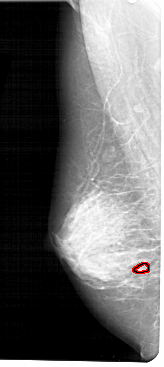

FILE: A_1280_1.LEFT_MLO.OVERLAY

TOTAL_ABNORMALITIES 1

ABNORMALITY 1

LESION_TYPE CALCIFICATION TYPE PLEOMORPHIC DISTRIBUTION CLUSTERED

ASSESSMENT 4

SUBTLETY 2

PATHOLOGY BENIGN

TOTAL_OUTLINES 1

BOUNDARY